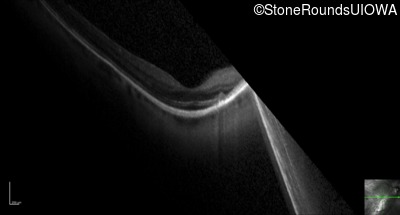

Optical Coherence Tomography - Right - 20/40 +2

Exemplar / OCT Stack

OCT Stack